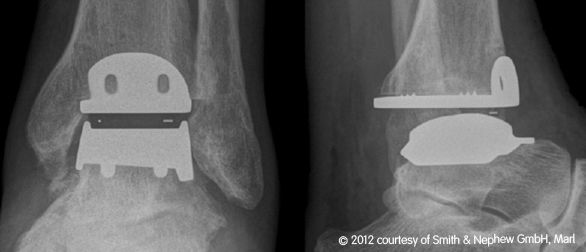

Obere Sprunggelenksendoprothese

Seit 2003 werden in unserer orthopädischen Abteilung in geeigneten Fällen die arthrotisch oder unfallbedingt zerstörten Sprunggelenke durch ein „künstliches Sprunggelenk“ ersetzt.

Wir verwenden dabei die von Prof. Hintermann entwickelte HINTEGRA-Totalendoprothese ,die zementfrei mit nur geringer Knochenresektion eingebaut wird.

Der Vorteil gegenüber der Arthrodese (Versteifung) ist evident: die Beweglichkeit im oberen Sprunggelenk bleibt erhalten oder wird teilweise wiedergewonnen, die bei der Versteifung gefürchtete Arthrose der benachbarten Gelenke wird vermieden. Die überwiegende Zahl der von uns behandelten Patienten ist bisher hoch zufrieden.